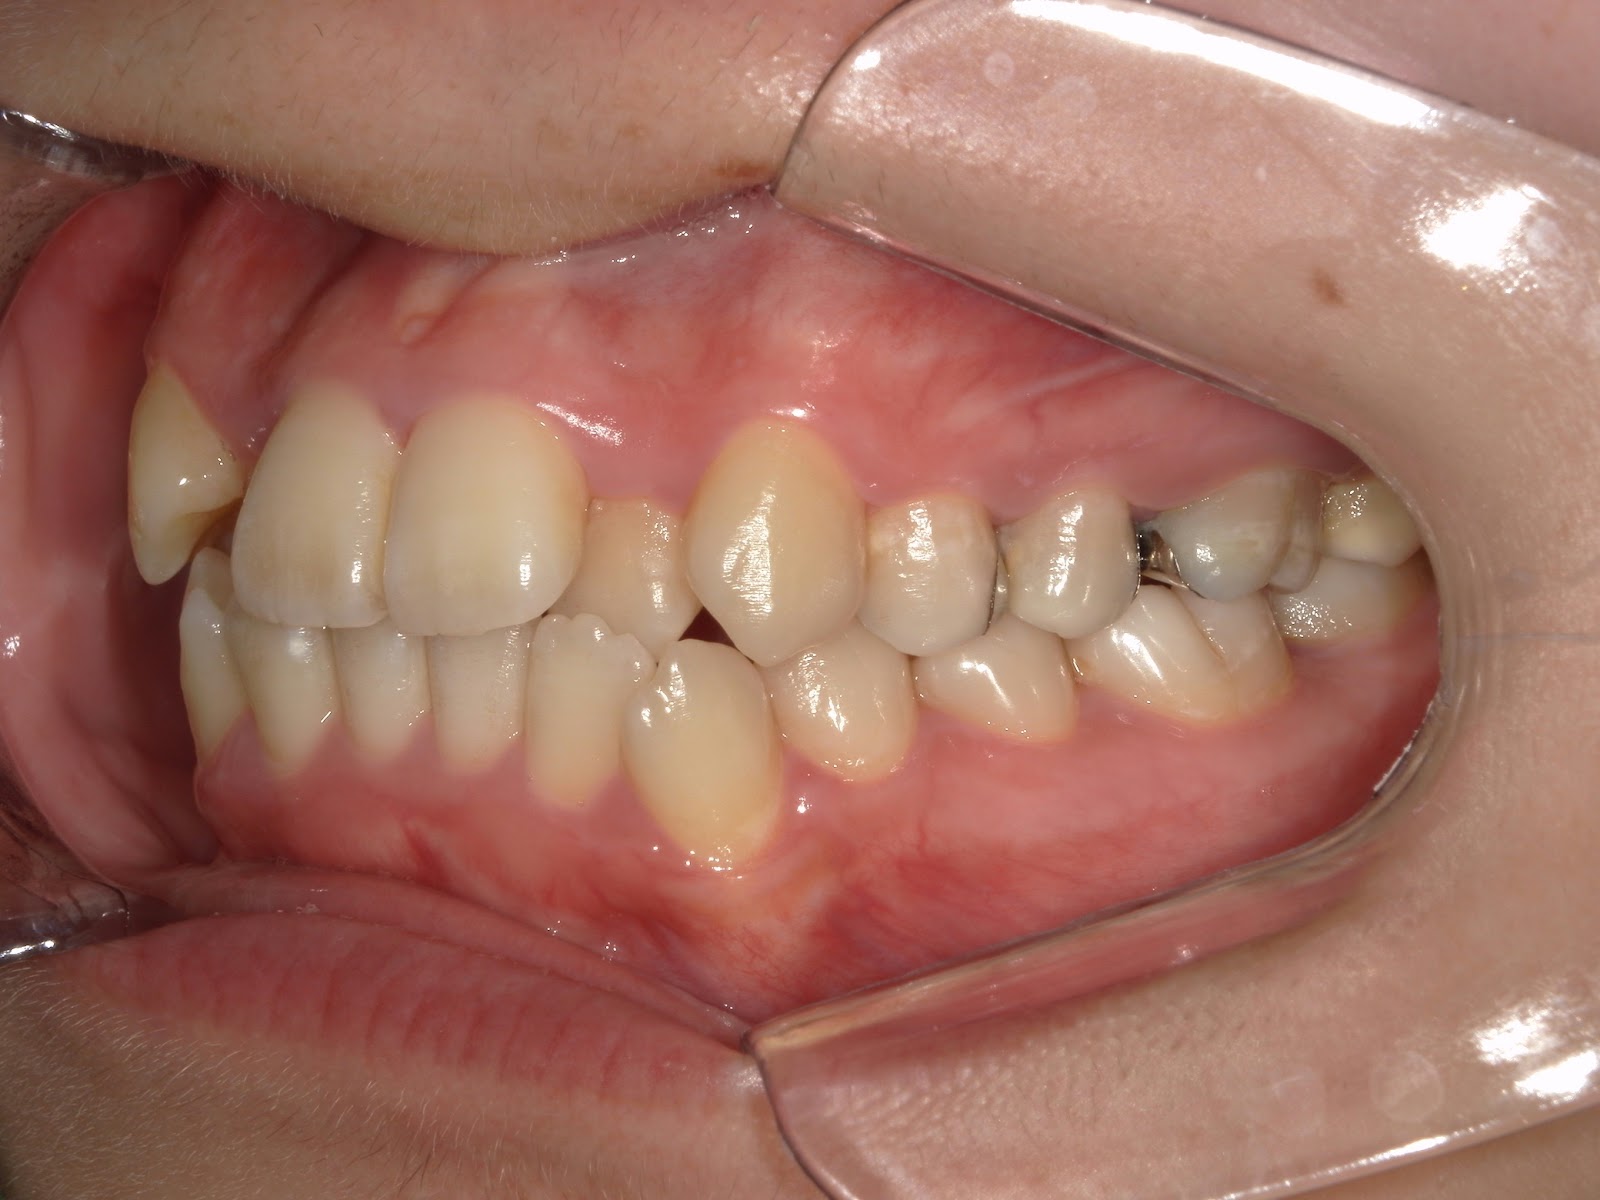

叢生歯列 治療例

治療後

| 患者様 | 女性 21歳 |

|---|---|

| 主訴 | 歯並びがガチャガチャしているので治したい |

| 診断 | 叢生歯列不正咬合 |

| 治療方針 | 上顎右側第一小臼歯、上顎左側第二小臼歯(第二小臼歯が根管治療歯のため当該歯を抜歯) |

| 治療に使用した装置 | マルチブラケット(セルフライゲーションブラケット) アンカースクリュー×1 |

| 治療期間 | 1年6カ月 |

| 治療回数 | 18回 |

| 治療費(自費診療) | 矯正治療費総額824,000円(税込み) |